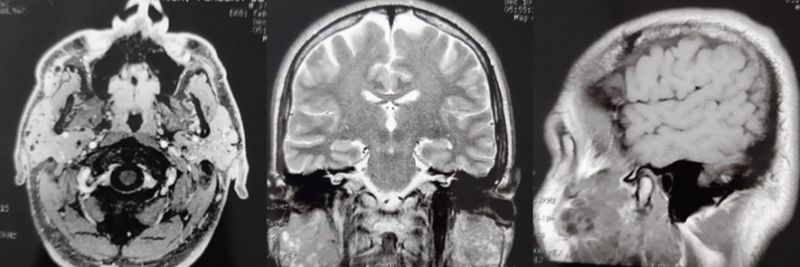

On cervical ultrasound, enlarged parotid glands were observed, especially on the left, with a heterogeneous diffuse texture, characterized by solid-cystic air (predominantly solid) and hypoechoic, affecting the entire parenchyma with diffusely increased flow. Numerous small bilateral diffuse cervical lymph nodes, mainly on the left, with an indeterminate appearance. Magnetic resonance imaging of the skull revealed images suggestive of multiple microcysts in the parotid glands, as shown in figure 1.

Figure 1: Magnetic resonance imaging of the skull, axial, coronal and sagittal sections, showing images suggestive of countless microcysts in both parotid glands.

Thus, in evaluating the imaging exams, there were findings suggestive of chronic sialoadenitis affecting the salivary glands, and it was not possible to rule out a lesion of another nature, with differential diagnoses being chronic parotitis, cystic lesion or even Sjogren's syndrome.